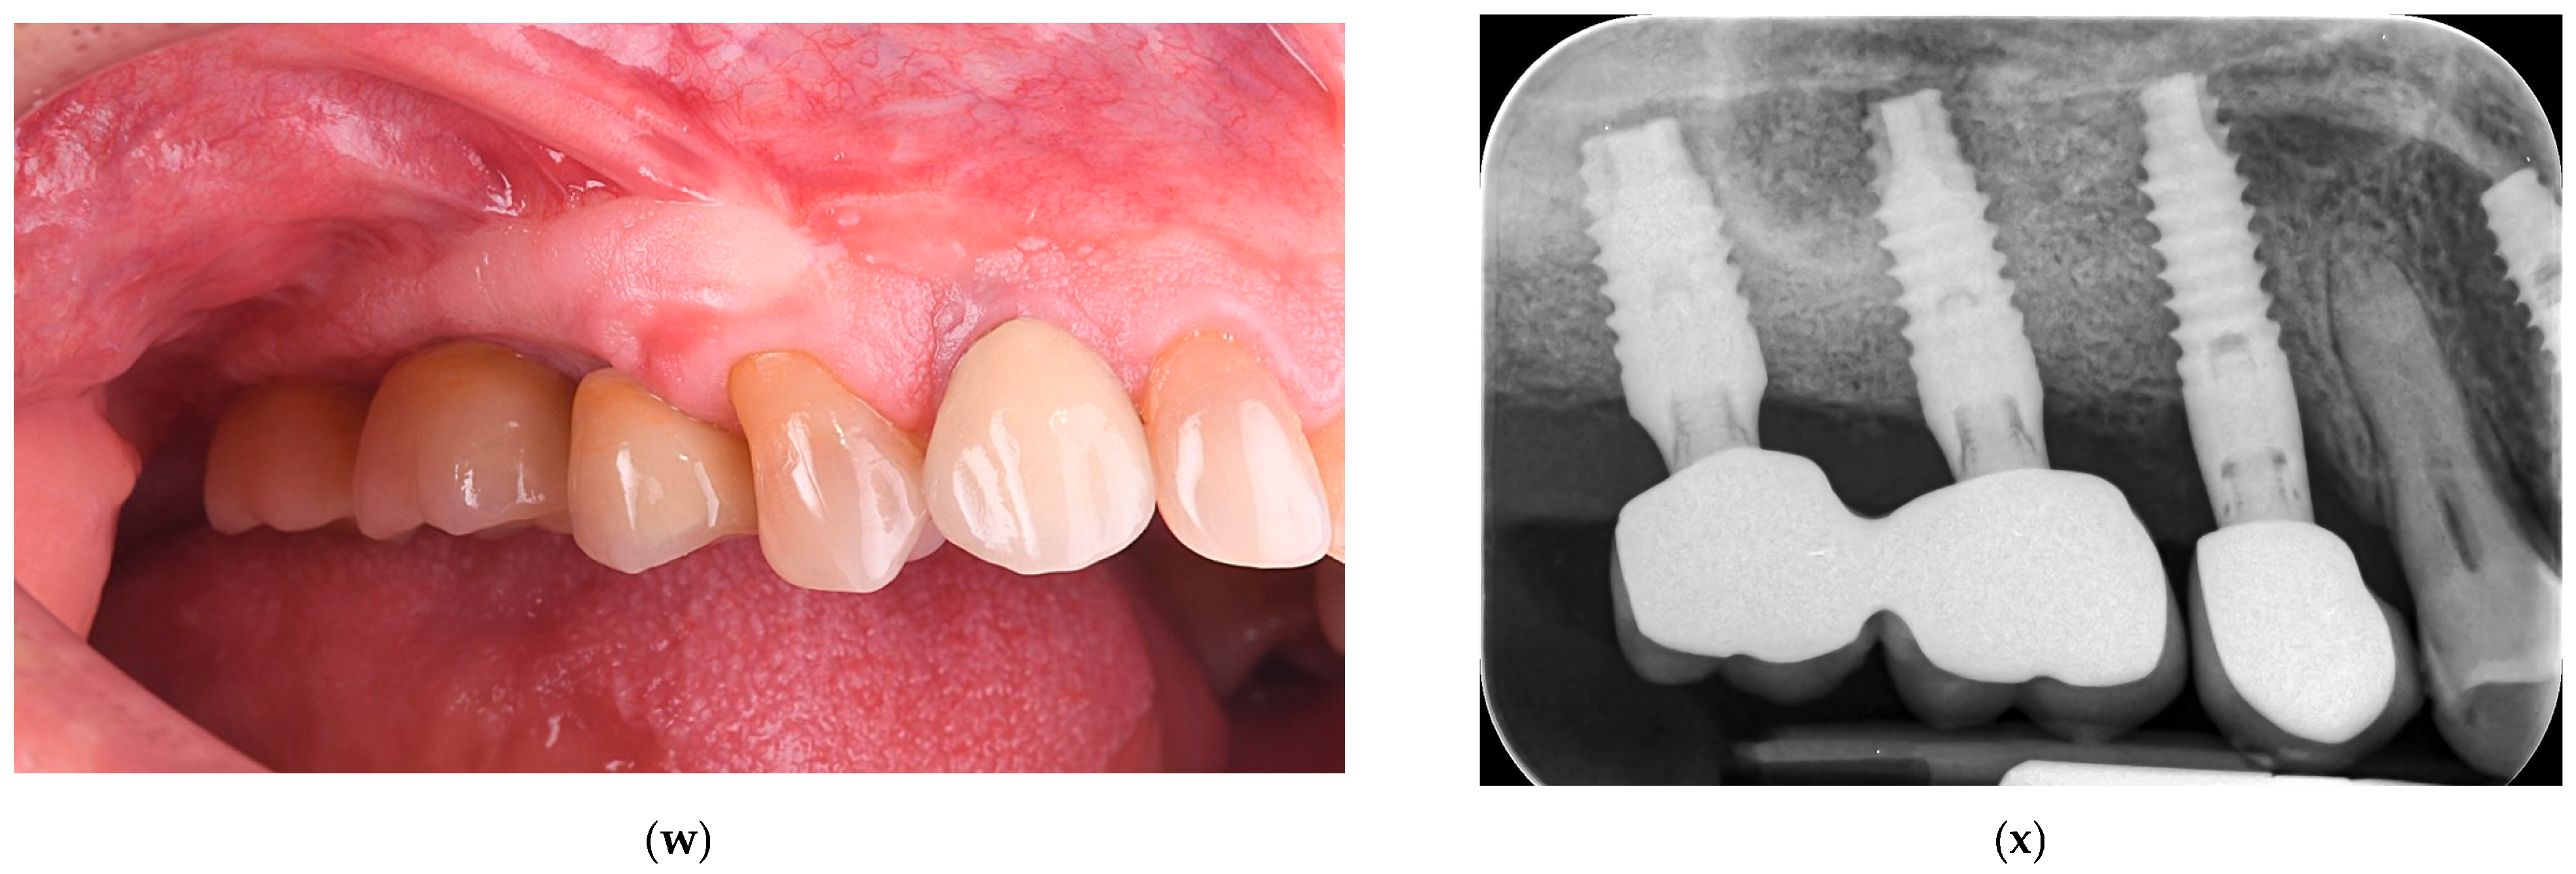

| 1. | F | 49 | 24 May 2021 | Lateral sinus lift with staged implantation | none | none | 4.7 | 2.5.; 2.6.; 2.7. | 2 | 15 | 13 | 52.23 |

| 2. | M | 56 | 9 August 2021 30 November 2021 |

| Intentional perforation for mucocele removal | none | 3.7 | 1.5.; 1.6.; 1.7. | 1 | 10 | 9 | 49.73 |

| 3. | M | 46 | 22 July 2021 | Lateral sinus lift with staged implantation | none | 7.5 | 2.6.; 2.7. | 1 | 15 | 14 | 38.3 | |

| Mean value | - | - | - | - | - | 5.3 | - | 1.33 | 13.33 | 12.0 | 46.75 | |

| Months 12–52 | Follow-up period | Stable marginal bone levels (<1 mm first year); no complications; graft volume maintained |

| 46.8 months (mean) | Long-term evaluation | All implants functional; radiographic and clinical stability confirmed |

| 52.2 months (max) | Long-term | CBCT and periapical radiographs from available case demonstrating stable bone height and osseointegration |